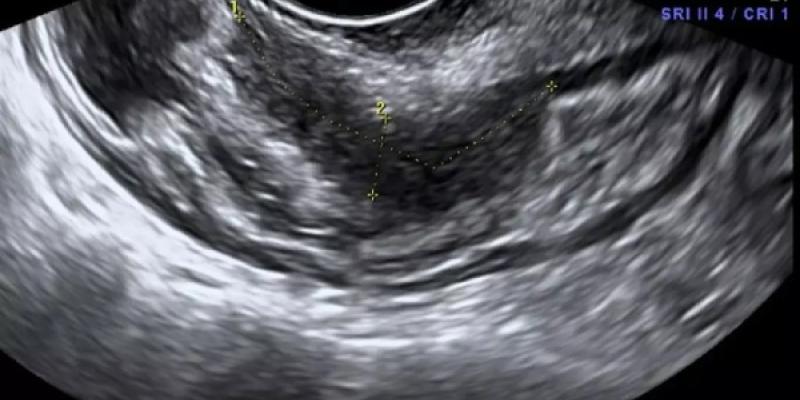

Endometrio tras una ecografía